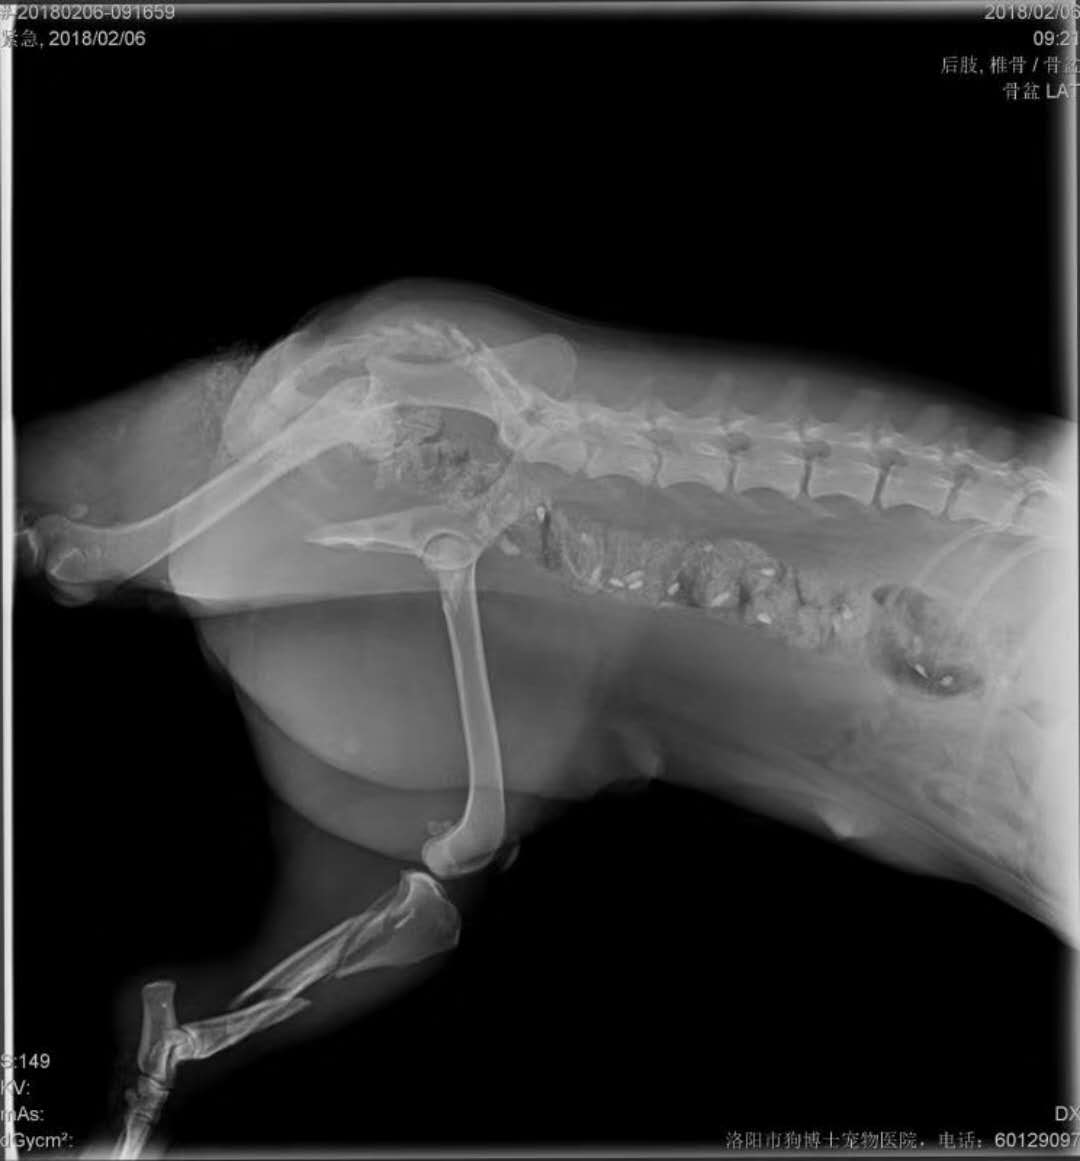

救助粉碎性骨折狗狗籌善款:好心人 常先生 于今早在王城大道與中州路口附近,救助一條黑色泰迪,昨后腿疑似被外力擊打致粉碎性骨折,送至我院進(jìn)行治療,因病情較重,治療費(fèi)用較高,現(xiàn)向社會籌集救助善款,捐款者可以直接發(fā)到劉鳳軍院長微信上(13698844707),您的善舉可以還狗狗一個健全的身體,感謝大家捐款或者轉(zhuǎn)發(fā)。